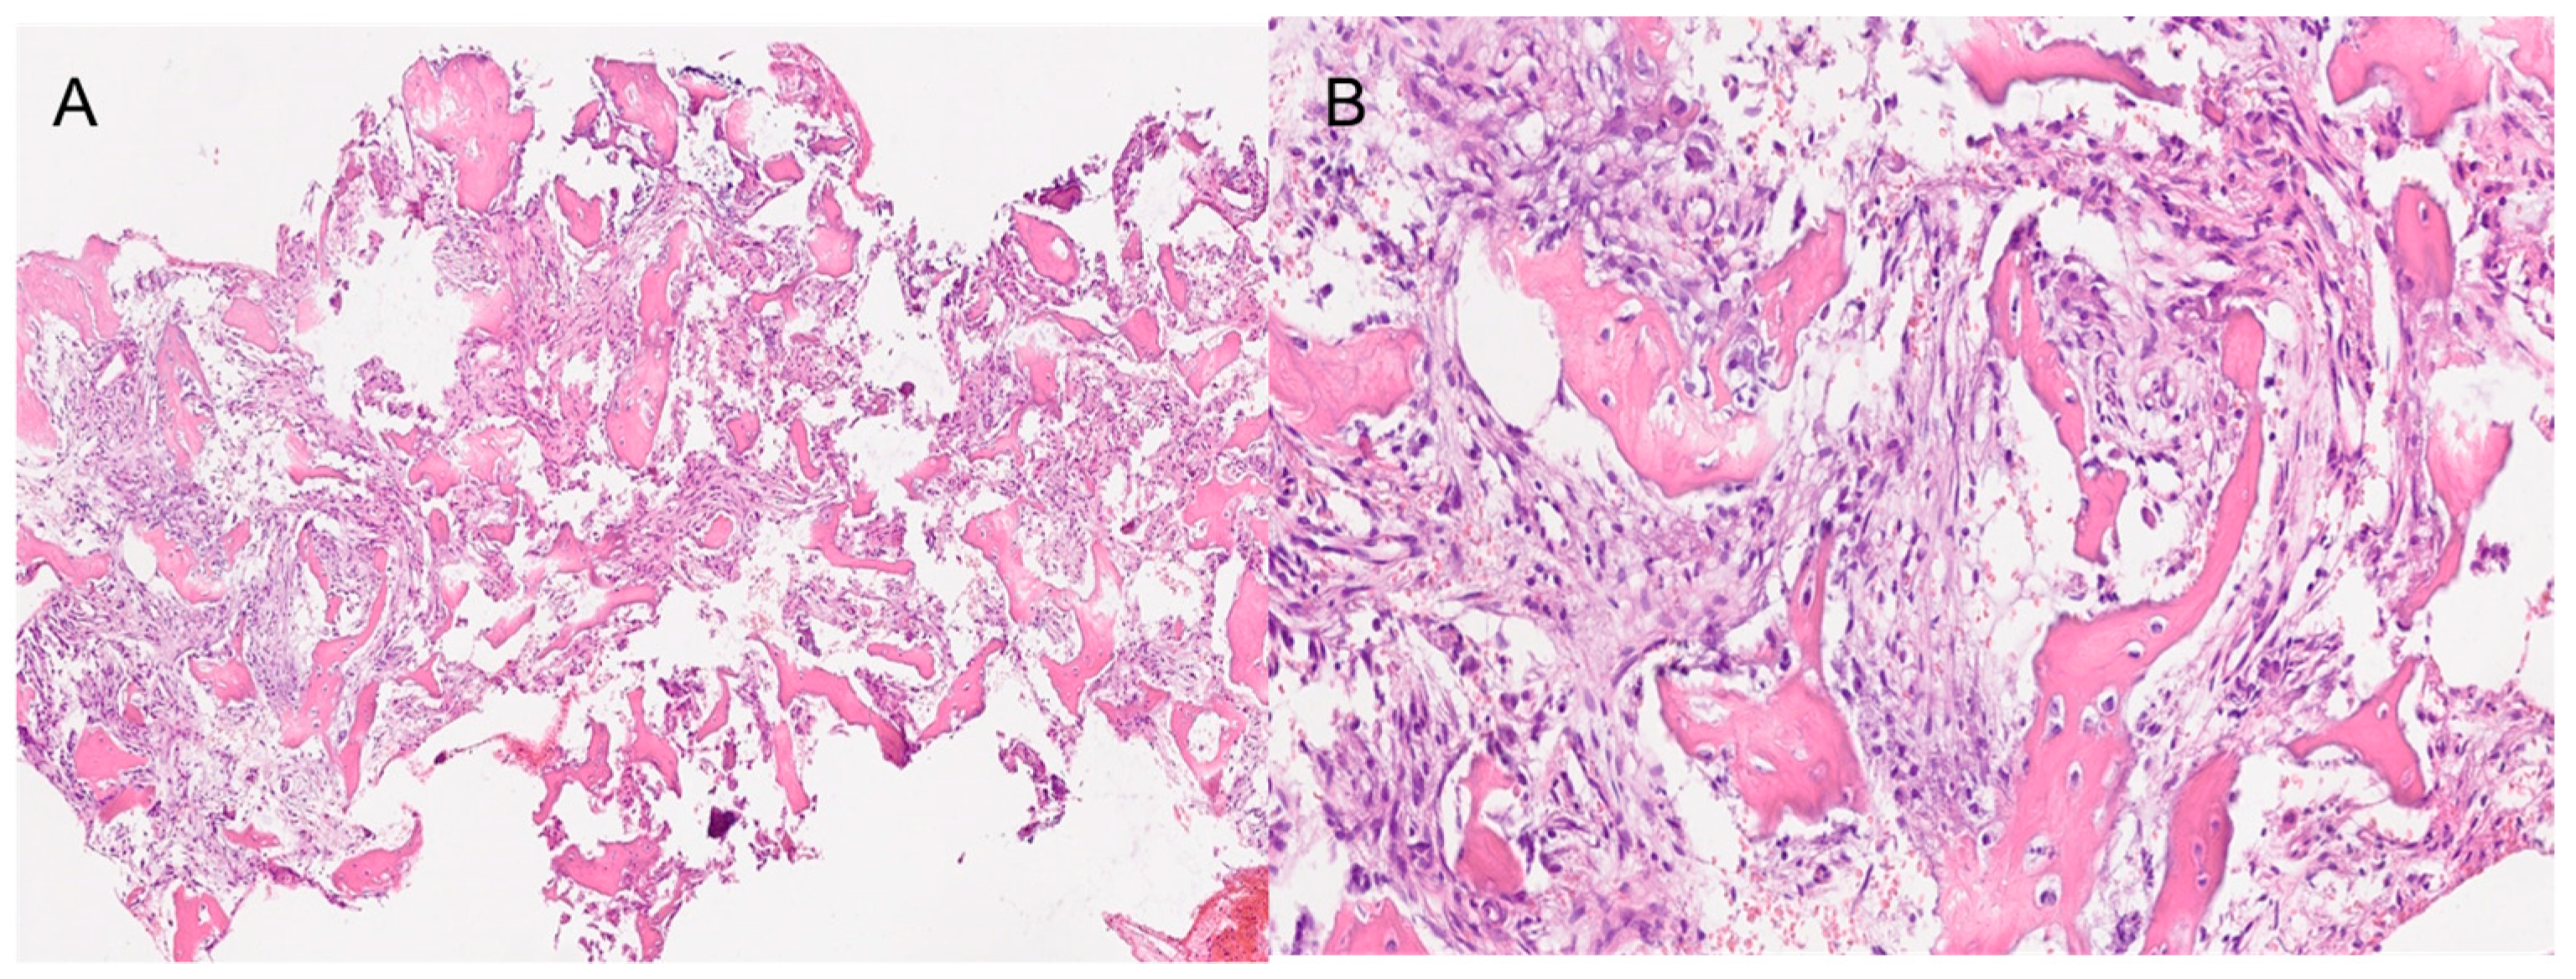

Both histological reports confirmed the diagnosis of fibrous dysplasia, showing a bone-fibrous fragment including bone trabeculae with irregular distribution with a crossed fibers structure with marked remodeling, and a non-atypic fibrous tissue with several vascular structures with thick and mineralized walls (Figure 3).

Moreover, in continuity with this tissue, they showed a de-epithelialized mucosa with normal gland structures. The Ki67 expression shown was <5%.

The histological result of the sample sent in the second surgery was Cemento-Ossifying Fibroma, a surprising result as this type of ossifying fibroma of odontogenic origin usually affects the tooth-bearing region of the gnathic bones (Figure 7).

Figure 7. The histopathological images show a section of the bones samples. (A) 4× magnification. (B) 20× magnification. Both images show the fibrous component with variable, medium to low cellularity. Osteoblastic rimming is observed in all trabeculae. The osseous component exhibits amorphous crystalline, calcific deposits. Segments of respiratory-type epithelium with areas of squamous metaplasia are also observed.